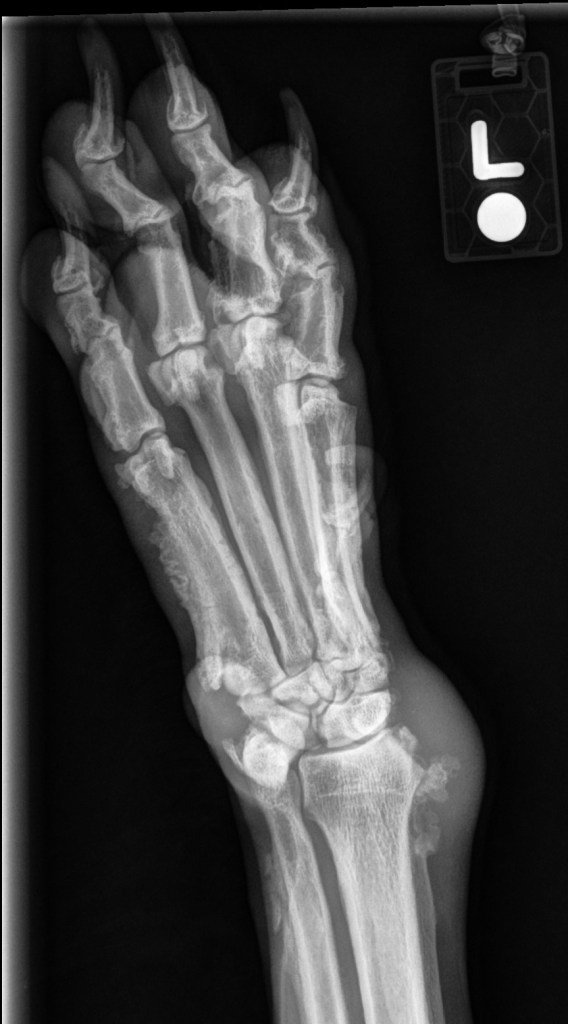

9yr FS Large Mixed Breed Dog. Swollen carpi and paws with progressive lameness.